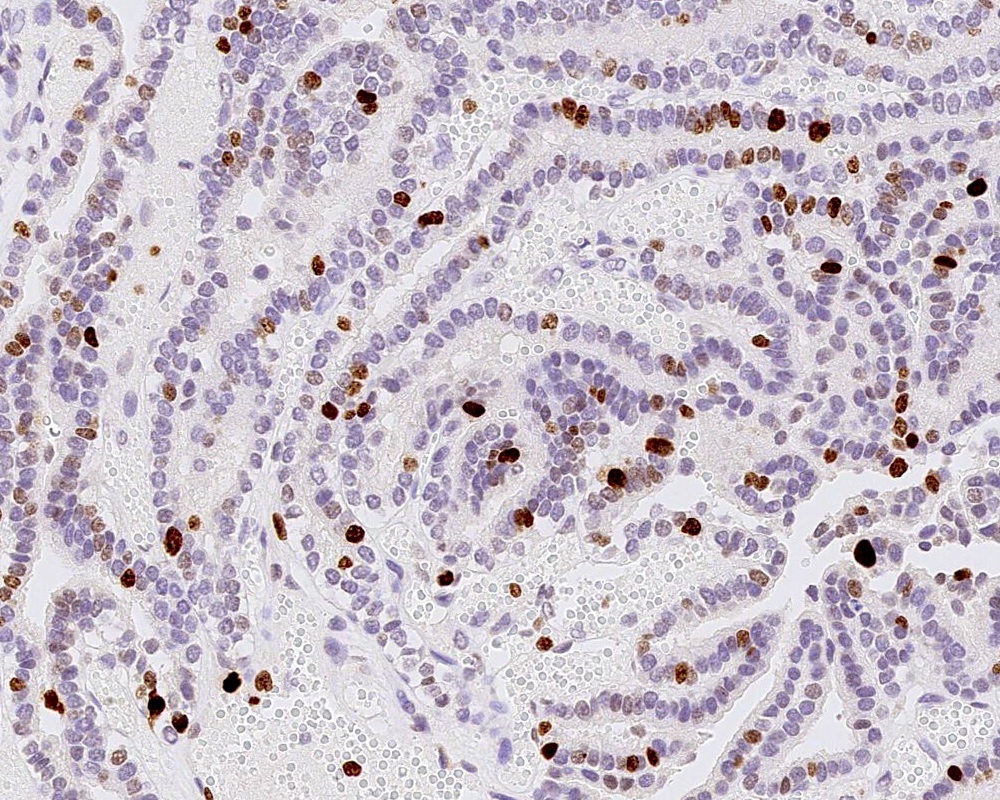

Microscopic (histologic) images

Positive stains

- Ki67 / MIB1 proliferation index may be used for grading (variable and subjective interpretation)

A 3 month old boy presented with restless crying and vomiting. His head size was larger than expected for his age. Imaging showed an 8 cm, lobulated, enhancing lesion in the right lateral ventricle. Histology is as above. Which of the following is true?

B. Recent studies suggest 3 distinct molecular entities based on methylation profiling, patient age and tumor location. An atypical choroid plexus tumor is shown in the image.